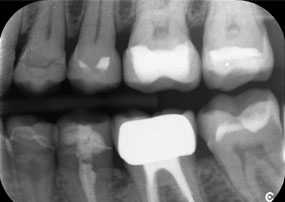

Otro ejemplo del rendimiento clínico de Power Edition fue la sustitución de una corona de zirconio dañada en una paciente de 63 años. El daño se produjo debido a la rotura de una parte del revestimiento de la corona de zirconio de 20 años de antigüedad en el diente 6. A pesar de encontrarse en la zona posterior, a la paciente le molestaba y deseaba una nueva corona.

La

material.

El

sentido.